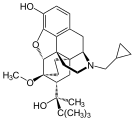

Several semi-synthetic opioids were developed in Germany in the 1910s. The first, oxymorphone, was synthesized from thebaine, an opioid alkaloid in opium poppies, in 1914.[228] Next, Martin Freund and Edmund Speyer developed oxycodone, also from thebaine, at the University of Frankfurt in 1916.[229] In 1920, hydrocodone was prepared by Carl Mannich and Helene Löwenheim, deriving it from codeine. In 1924, hydromorphone was synthesized by adding hydrogen to morphine. Etorphine was synthesized in 1960, from the oripavine in opium poppy straw. Buprenorphine was discovered in 1972.[228]